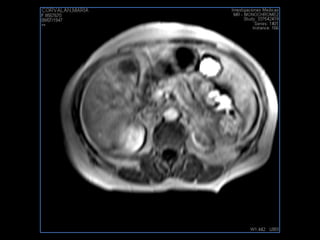

PROTOCOLO pancreas/ riñon AXIAL fat sat /AX in phase out phase AX T1 +SAG T2  COR T2, CON   GADOLINIO :  COR T1+AX T1(DIN) SAT: NO  FASE: RL THK: 4MM  COIL:  GAP: (FACTOR 1.4) 1MM FOV: 40 CM NEX:2 SINCRONIZACION RESPIRATORIA EN 3 O 4 CICLOS ALE

resonancia de abdomen